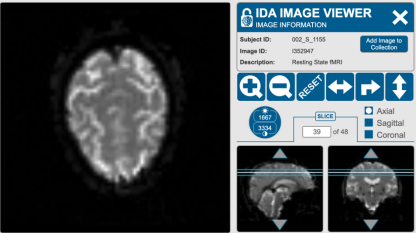

常见的功能性磁共振成像(fMRI)数据格式是DICOM(Digital Imaging and Communicationsin Medicine)。DICOM是医学影像领域的一种标准格式,用于存储医学影像数据,包括MRI、CT、PET等[7]。DICOM格式的fMRI数据通常包含多个序列,每个序列代表了一次扫描(即一个时间点),并包含了体积图像数据以及相关的元数据,比如扫描参数、患者信息等。这种格式在医学影像研究中广泛使用,并且可以方便地与其他医学影像工具和软件进行交互和分析。

图2 静息状态下不同位置人脑截面图[8]